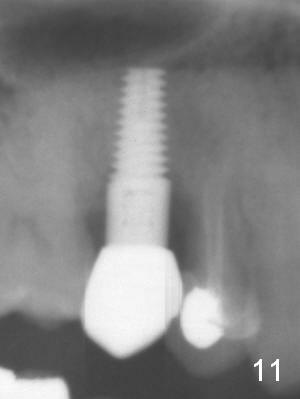

Osteotomes are used to form initial osteotomy, approximately 11 mm deep, 4 mm wide. Bicon reamers (Fig.3 R) are used to increase osteotomy while collecting autogenous bone; it appears that the sinus floor is partially penetrated (dashed line). After sinus lift (Fig.4 dashed line), a 5x14 mm cylindrical tissue-level implant is placed (I; arrowheads: sinus floor). There is no intraop nasal hemorrhage. Amoxicillin is prescribed postop (500 mg tid for 7 days). There is purulent, particulate discharge from the right nostril postop. One month later, the implant is loose and removed.

Four months after implant removal, the bony defect appears to increase (Fig.5). Reamers (Fig.6 R)and osteotome (Fig.7 O) are short of the sinus floor (arrowheads). A 5x14 mm tapered implant is placed with primary stability (Fig.8 I). The implant is placed ~ 2 mm deeper (Fig.9). No bone graft is used for sinus lift. There is no complication. The sinus floor appears to be repaired 4.5 months postop (Fig.10). Fig.11 (trimmed from panoramic X-ray) is taken 1 year 7 months post cementation. The bone remains stable 4 years 2 months post cementation (Fig.12); the mesial defect is most likely related to extraction trauma (*).